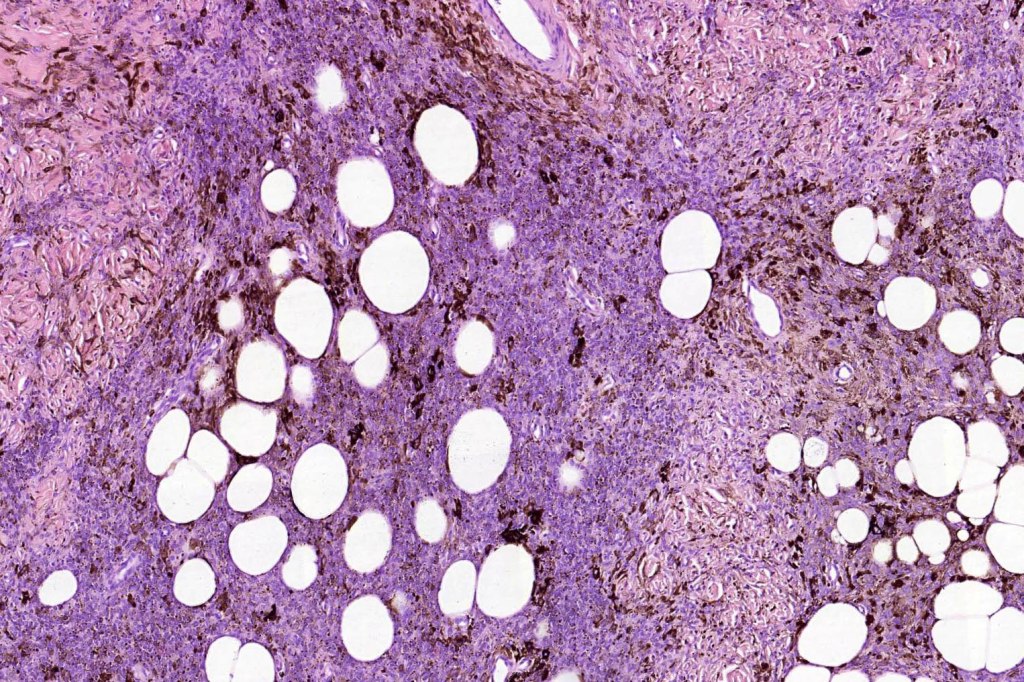

Combined common & deep penetrating nevus

Combined congenital & blue nevus (same case as the clinical photographs coursty of Dr. Antonina Kalmykova